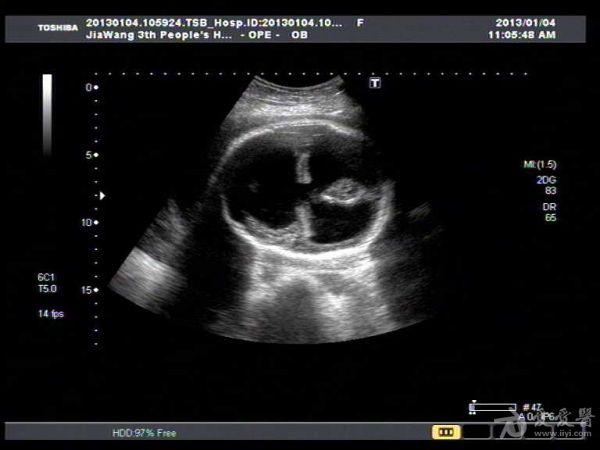

此孕妇听信家人说吃核桃能补脑,吃了两个月核桃来来复查,脑积水更明显。